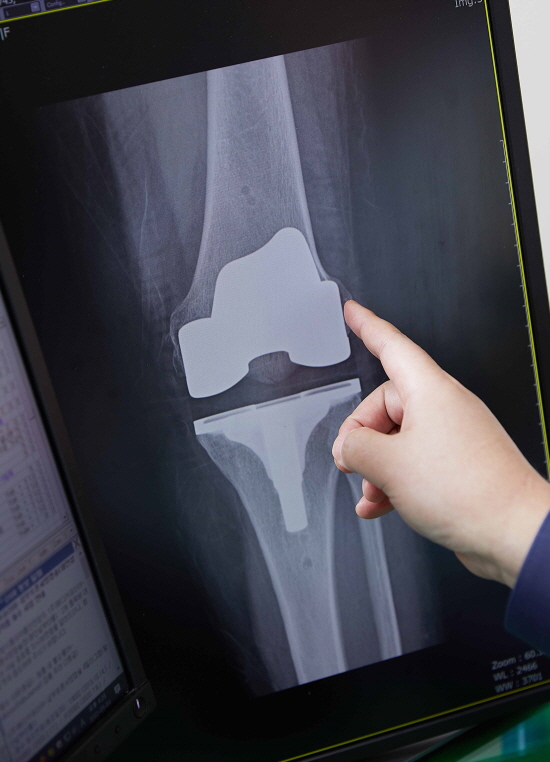

이미지

인공관절 수술 후 엑스레이 사진/신지호 헬스조선 기자